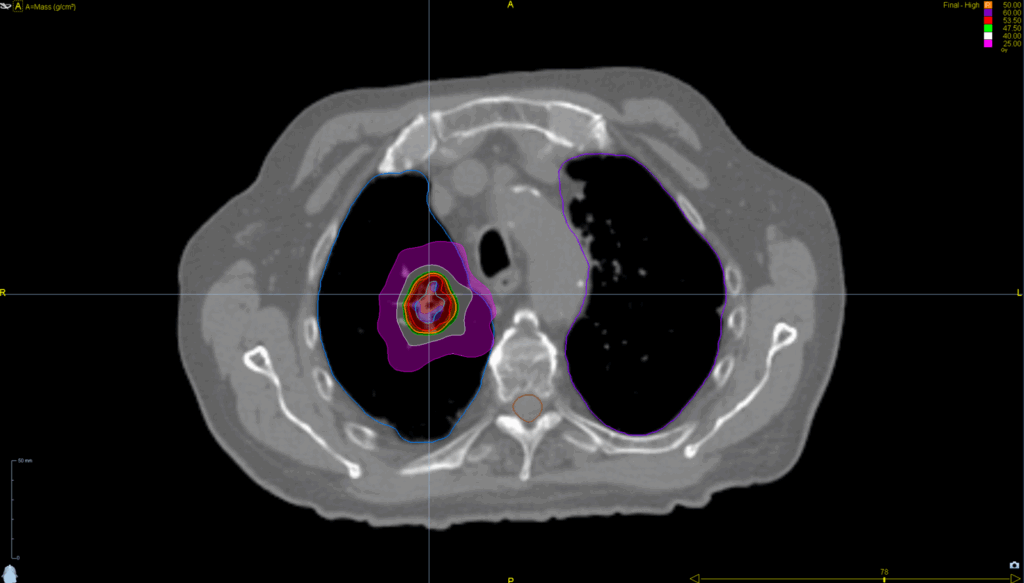

Treatment Plan Images

Fractionation / Protocol Used

50 Gy in 5 fractions

PTV(s) Volume

5 cm, 55 cc

Mode

- Tomohelical™

- Synchrony® Lung™

- SBRT

- TomoEDGE™ 2.5 cm